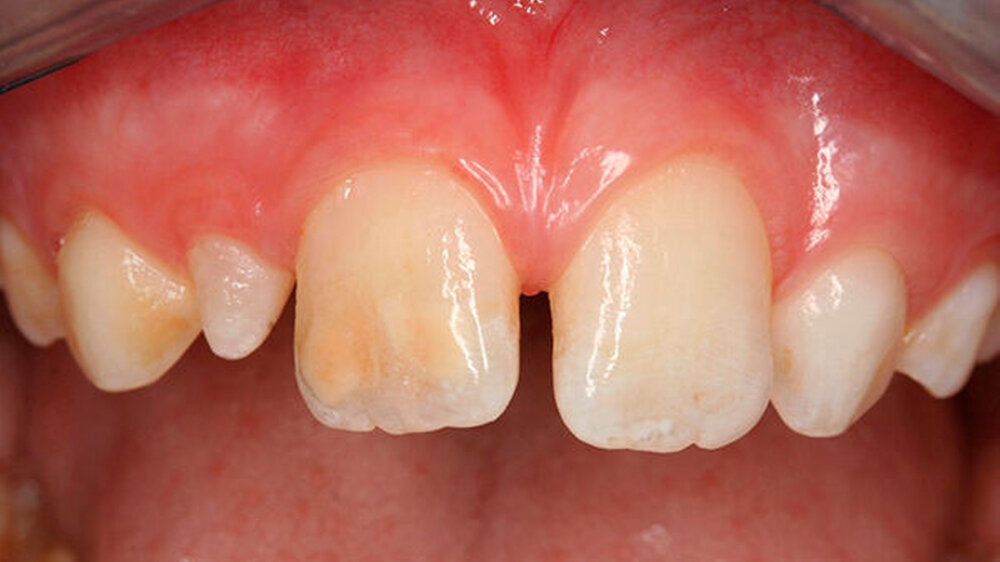

Das klinische Bild der MIH reicht von einem bis zu vier betroffenen Molaren, nur selten sind alle Zähne in ähnlicher Ausprägung geschädigt [Weerheijm et al., 2001]. Die bleibenden Frontzähne können ebenfalls betroffen sein, diese weisen allerdings in der Regel keinen Schmelzeinbruch auf und sind selten bis gar nicht überempfindlich [Weerheijm et al., 2001] (Abbildung 2).

Bisher wurde nicht beschrieben, dass die Frontzähne nur allein betroffen sein könnten. Meist wird - wenn die Frontzähne zusätzlich zu den Molaren betroffen sind - über mangelnde Ästhetik geklagt und die Kinder aufgrund ihres Aussehens gehänselt.

In schwerwiegenden Fällen kann der Einsatz eines Komposits das beste Ergebnis erzielen (Abbildungen 2, 13 und 14)